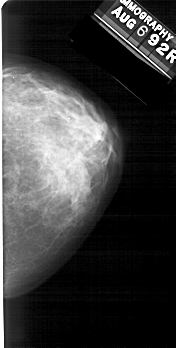

A_1391_1.RIGHT_CC

RIGHT_CC LINES 5206 PIXELS_PER_LINE 2626 BITS_PER_PIXEL 12 RESOLUTION 43.5 NON_OVERLAY